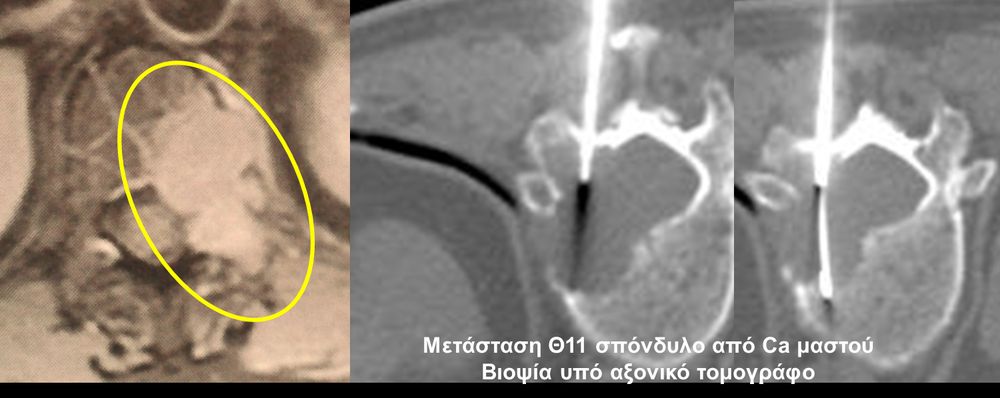

Η οστική βιοψία και η βιοψία όγκων μαλακών μορίων χρησιμοποιείται για την ιστολογική διάγνωση αλλοιώσεων (καλοήθων - κακοήθων / πρωτοπαθών ή μεταστατικών) ή για τη λήψη υλικού προς καλλιέργεια ώστε να αναδειχθεί το μικρόβιο που προκαλεί τη λοίμωξη του μυοσκελετικού συστηματος (πχ σπονδυλοδισκίτιδα). Η βιοψία υπό συνεχή απεικονιστική καθοδήγηση συμβάλλει στην υψηλή ακρίβεια τοποθέτησης της βελόνης εντός της βλάβης με ασφαλή προσπέλαση. Η χρήση σύγχρονων ομοαξονικών συστημάτων βιοψίας (coaxialtechnique) επιτρέπει την λήψη πολλαπλών δειγμάτων με μια μόνο παρακέντηση.